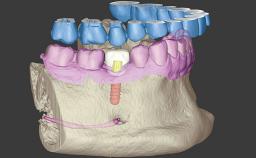

A 60-year-old healthy male patient presented with problems involving a fixed dental prosthesis (FDP) in the lower left quadrant. The bridge had de-cemented from abutment teeth 33 and 35; tooth 33 was decayed, and tooth 35 had little structure remaining. Since removing the FDP spanning sites 33 to 38 would have compromised function and raised esthetic concerns, the possibility of immediate implant placement and provisionalization was investigated.